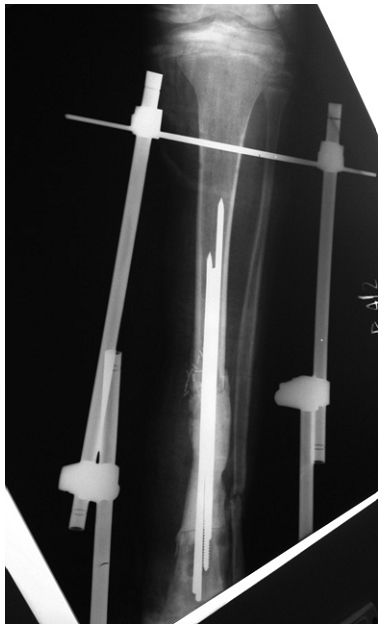

➤ 1、I期取掉内固定物;

➤ 2、彻底清创;

➤ 3、采用带抗生素的骨水泥做成的spacer(间隔块),比如下图里用3根克氏针+骨水泥做成的间隔块;

➤ 4、并用外固定支架支撑。